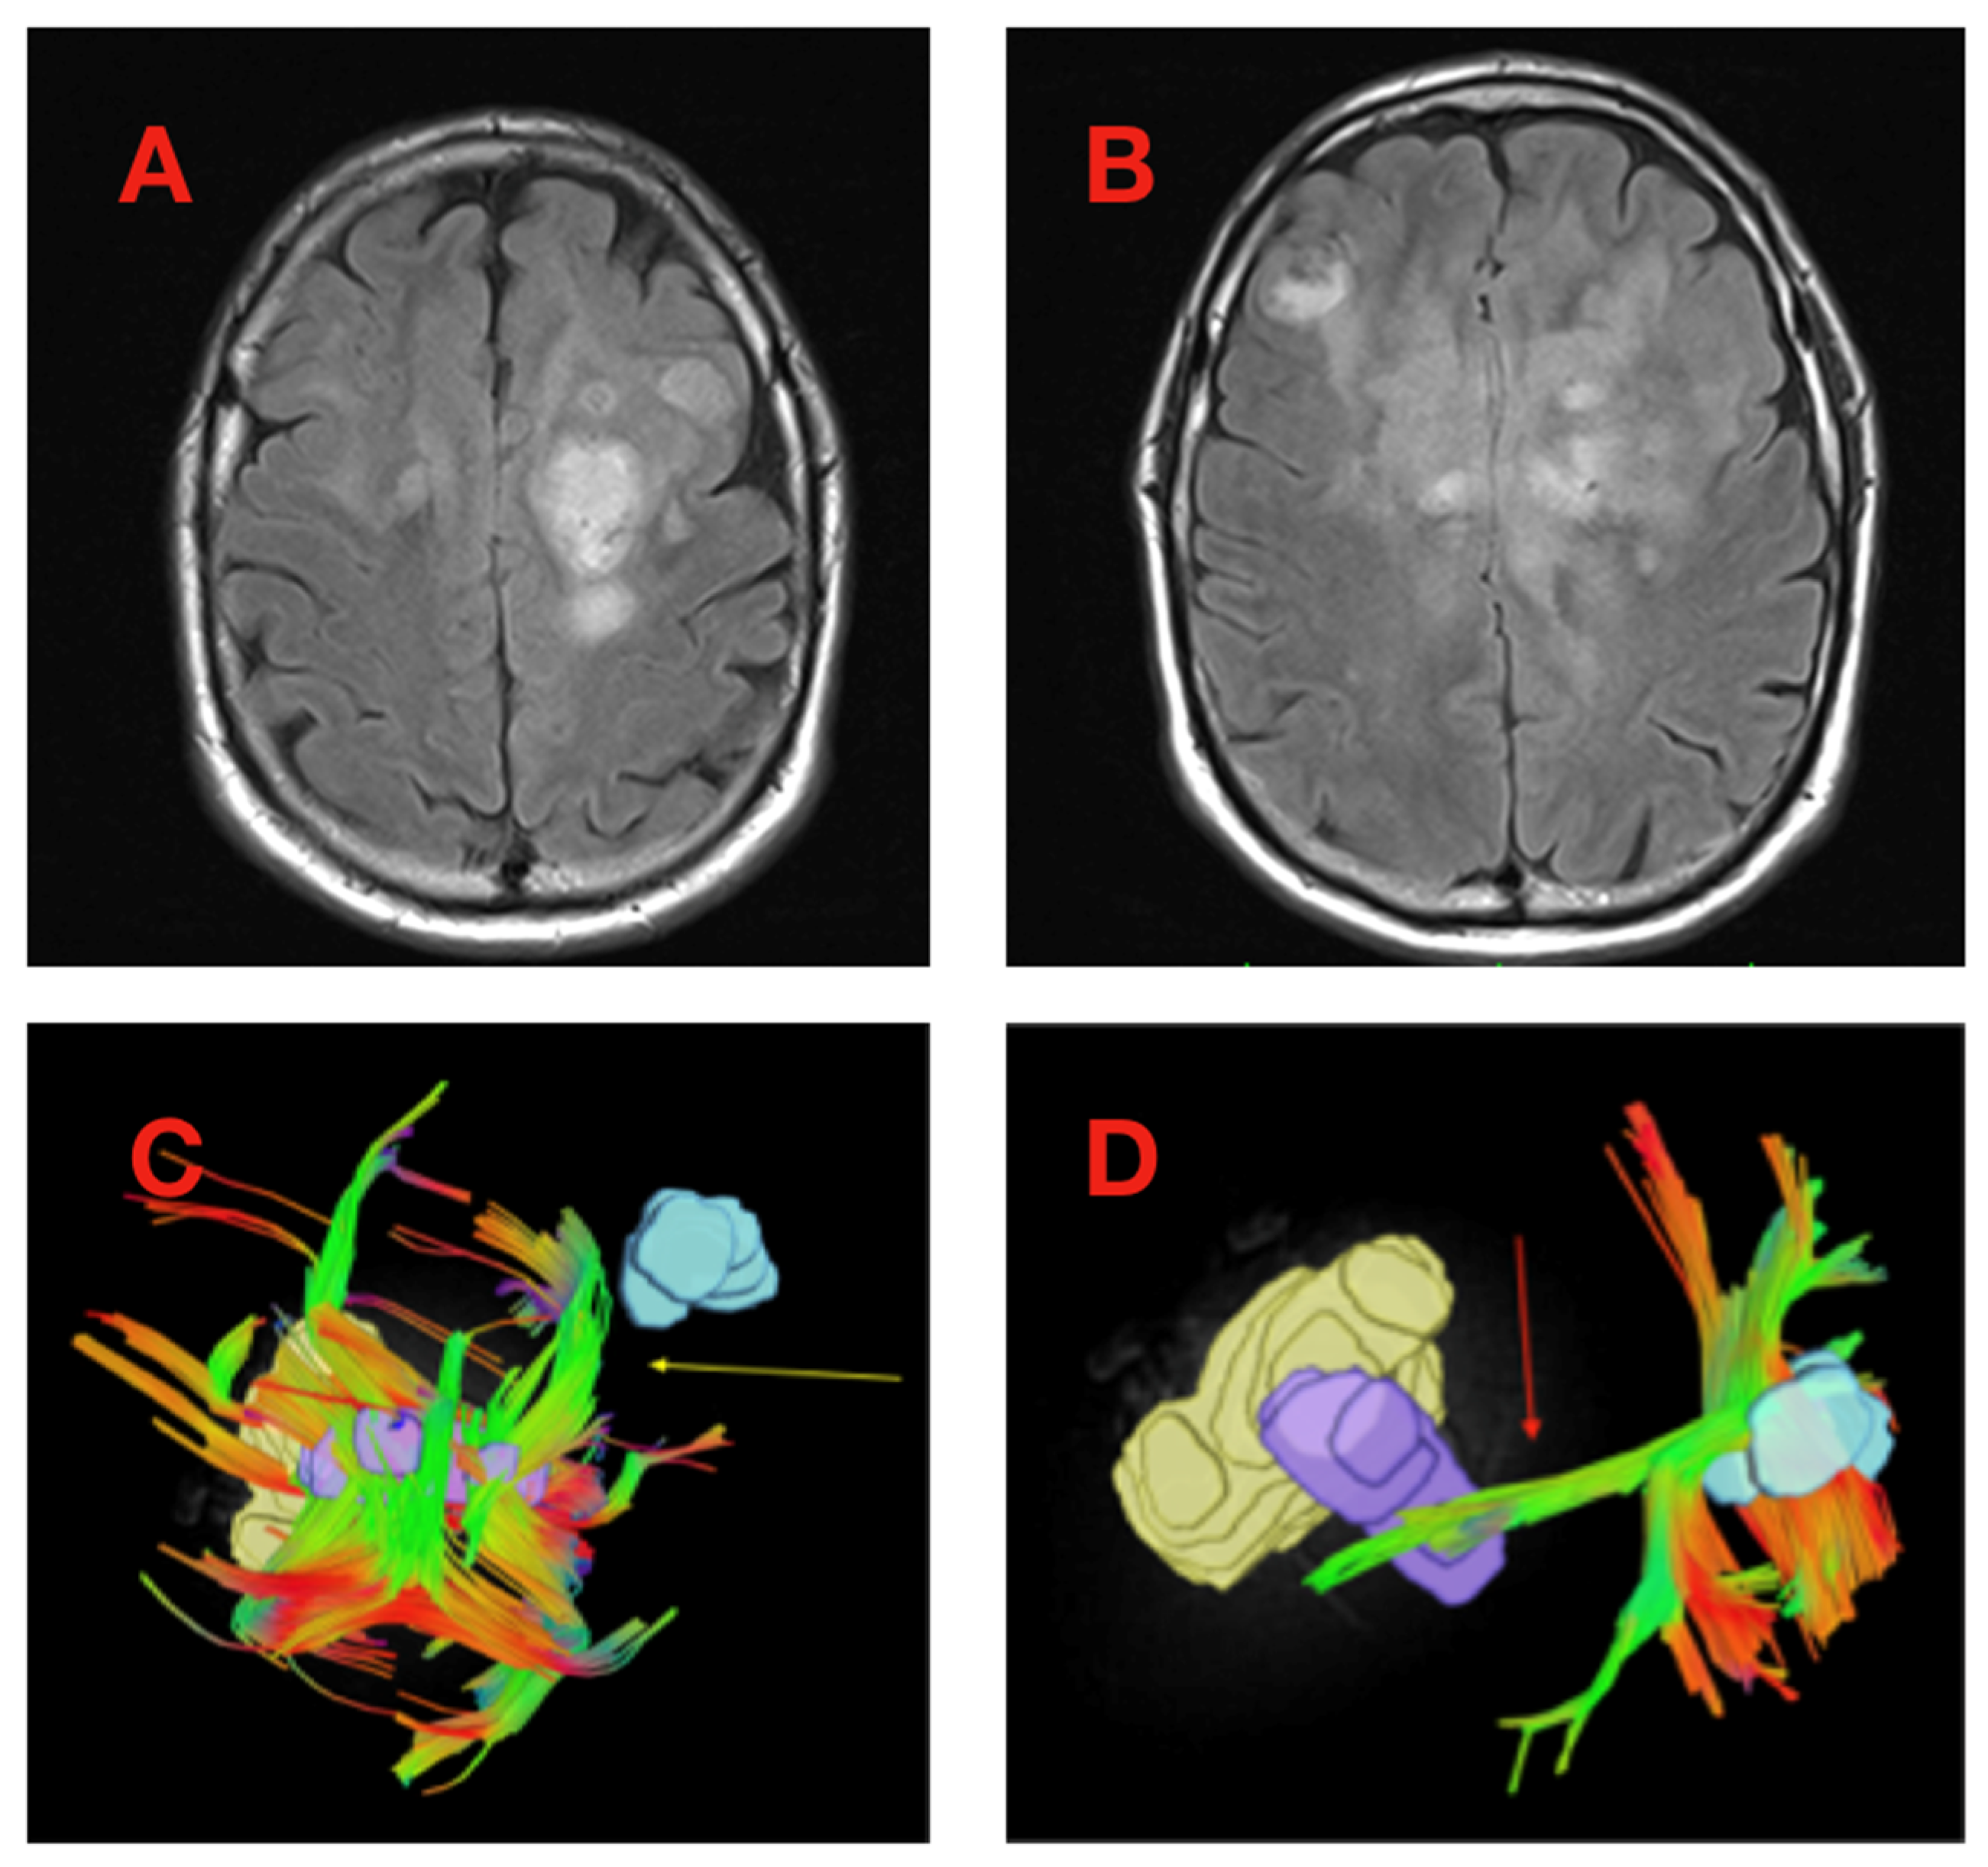

| Location, Corpus Callosum | 4 (6.1%) | – | <0.001 |

| Corpus Callosum | 34 (51.5%) | – | 0.091 |

| Inferior Longitudinal Fasciculus/Inferior Frontal-Occipital Fasciculus | 20 (30.3%) | – | 0.008 |

| Mean Tract Length (mm) | 29.1 (±11.7) | −7.79 (−21.88, 6.31) | 0.274 |